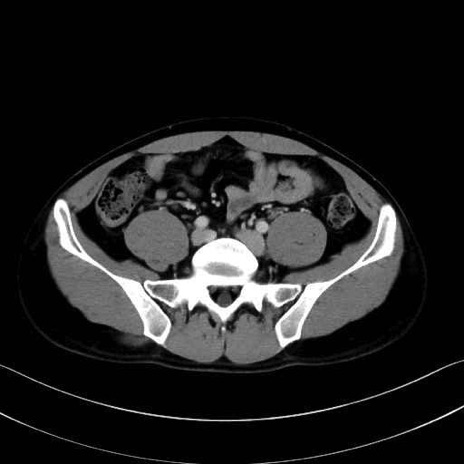

腰方形筋(quadratus lumborum muscle)のCT画像の解剖

腰方形筋 (Quadratus lumborum)